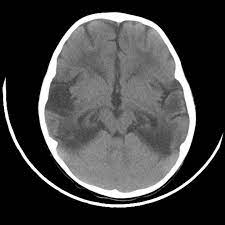

Two subtypes are recognised which differ in demographics, virus, and pattern of involvement. Mri demonstrates extensive edema in the right temporal lobe with areas of intrinsic high t1 signal, in keeping with hemorrhage. Terminology the entity or closely related variants have also been. Coccidioidal meningitis refers to central nervous system involvement of the dimorphic fungus coccidioides spp, mainly coccidioides immitis and coccidioides posadasi. Note the high signal in the caudate heads and putamen on flair.

Pcr was repeated on the biopsy specimen and was positive for hsv. Limbic encephalitis, mca ischaemia, tumours, effects of seizures) hyperintense t2 signal in the medial temporal lobes, inferior frontal lobes and insula basal ganglia are usually spared Axial t2 prominent swelling, increase t2 signal involving the left temporal lobe and insular cortex. Multilocularis, and describes a spectrum of disease involving the spinal cord, the spine, or both. Mri is the diagnostic modality of choice abnormal in 90%; A brain biopsy was performed and the histology was consistent with encephalitis. Mri demonstrates extensive edema in the right temporal lobe with areas of intrinsic high t1 signal, in keeping with hemorrhage. For a general discussion, and for links to other system specific manifestations, please refer to the article on hydatid disease.

The changes spare the basal ganglia, a feature which is helpful in distinguishing an mca infarct with hemorrhagic transformation from herpes simplex encephalitis, the diagnosis in this case. Hse may result from primary infection or reactivation from latency, and it frequently involves frontal or temporal lobes, as well as the brain stem. Herpes simplex (hsv) encephalitis is the most common cause of fatal sporadic fulminant necrotizing viral encephalitis and has characteristic imaging findings. It is usually bilateral but asymmetrical. The differential diagnoses include limbic encephalitis (paraneoplastic), gliomatosis cerebri, and status epilepticus. Two subtypes are recognized which differ in demographics, virus, and pattern of involvement. Given the history of fever and seizures coupled with the mri findings of bilateral mesial temporal lobe changes, herpes encephalitis requires clinical consideration. Spinal hydatid disease is an uncommon manifestation of hydatid disease, caused by the larval stage of echinococcus granulosus, or less commonly e. Multilocularis.the larval stage is the cause of hydatid disease in humans 1. The differential diagnoses include limbic encephalitis (paraneoplastic), gliomatosis cerebri, and status epilepticus. Herpes simplex encephalitis (hse) is the most common form of viral sporadic encephalitis and, when left untreated, has a mortality rate of 70% (3, 22). This patient went on to have hsv encephalitis proven on csf pcr. Bilateral temporal lobe t2 hyperintensity refers to hyperintense signal involving the temporal lobes on t2 weighted and flair imaging.